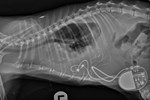

Commenting on Rusty’s presentation prior to treatment, Professor David Church, Deputy Principal and Acting Vice-Principal (Clinical Affairs) said: “Rusty was diagnosed with diabetes mellitus by his primary care vets in early 2019, but achieving control of his condition quickly became very difficult. Investigation of the reasons for this confirmed Rusty had a tumour in his pituitary gland at the base of his brain, producing hormones that not only stopped insulin working properly and causing his diabetes, but they also made his diabetes almost impossible to control. This had meant he had lost a great deal of weight despite a huge appetite and was also not his previous happy self.”

Surgeon Joe Fenn, Lecturer in Veterinary Neurology and Neurosurgery, added: “Until quite recently there would have been no reliably effective treatment options available for cats with Rusty’s condition. However, since 2012, the RVC team has been routinely performing hypophysectomy, the surgery aimed at removing the overactive pituitary gland tumour in cats, and we are extremely proud to say that Rusty was the 100th patient that we operated on.

“After a discussion between his owners and our Internal Medicine Service, Rusty was booked in for hypophysectomy surgery. His procedure went according to plan, allowing us to remove all of his pituitary gland tumour successfully, and after a short stay in our intensive care unit he was moved back to wards to continue his recuperation. Rusty responded very well to the surgery and was discharged a week later, no longer requiring insulin injections. To see Rusty back home enjoying life again with his owners and with his diabetes effectively cured is immensely rewarding, and we look forward to following his progress in the coming years.”